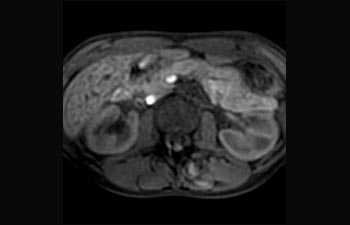

Sehen Sie selbst, was die ersten Nutzer von Ingenia Prodiva 1.5T über ihre Erfahrungen mit dem System und dessen Auswirkung auf ihre radiologische Praxis berichten.